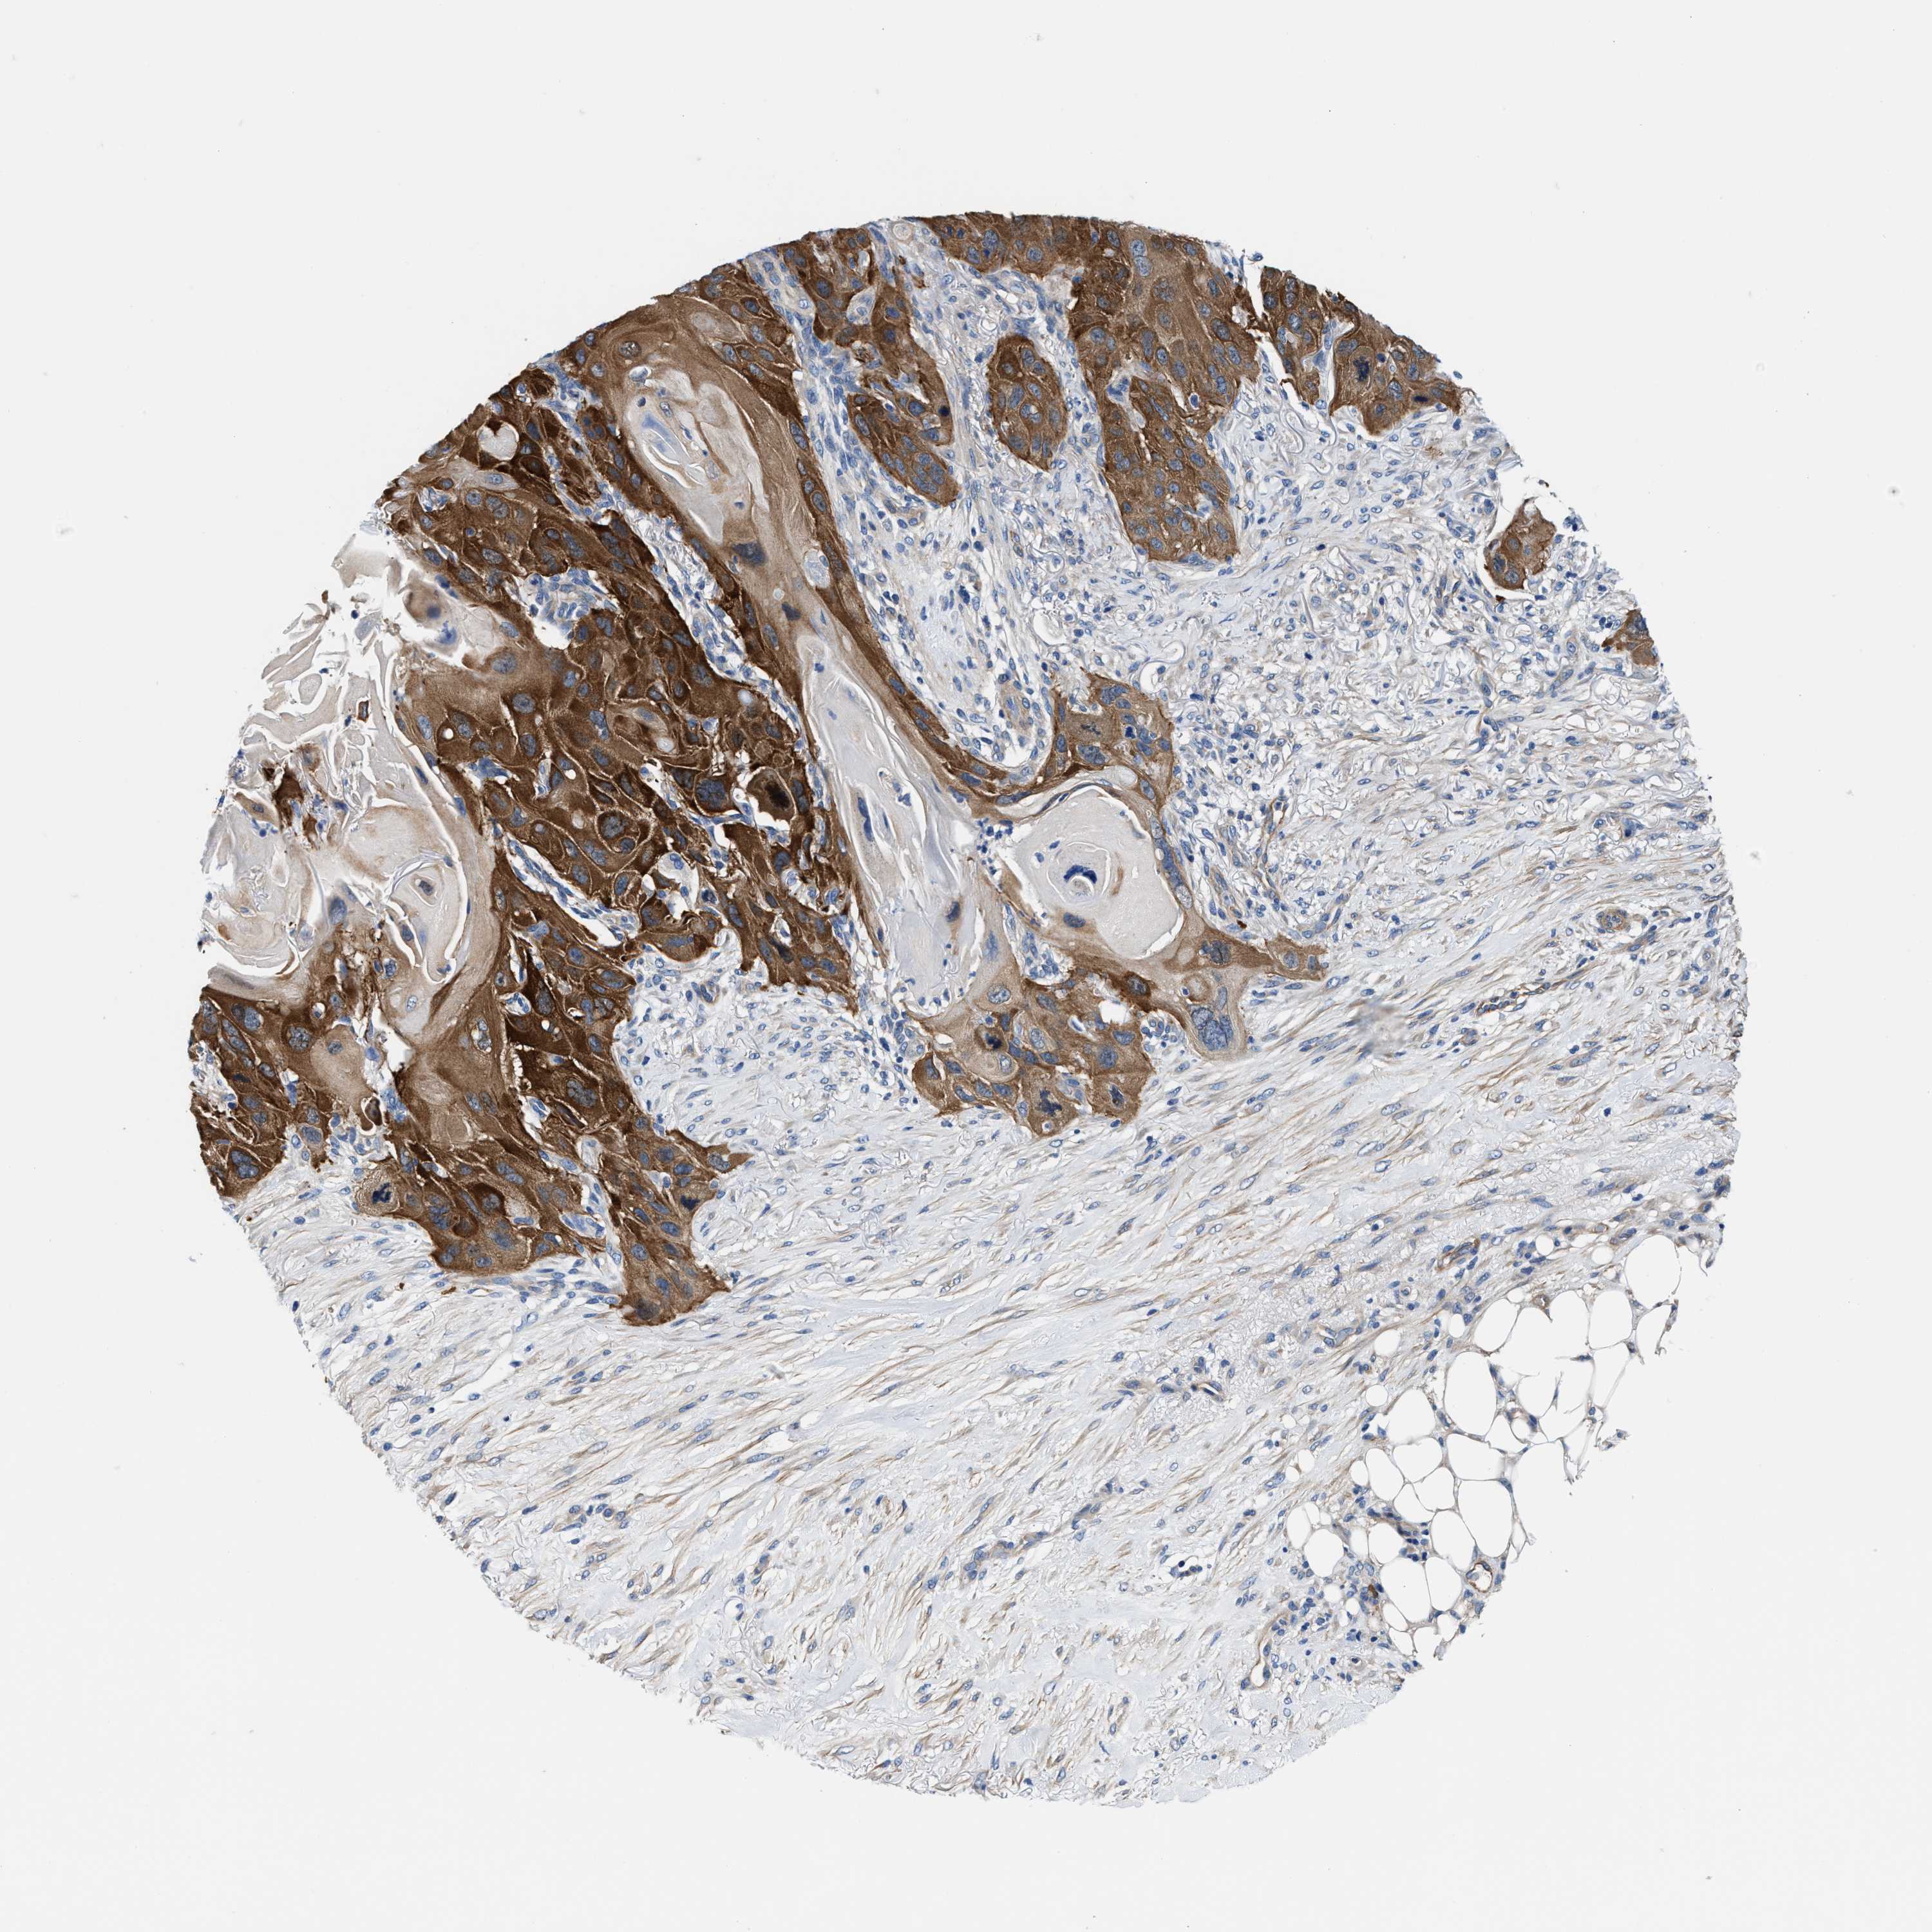

Basal cell and squamous cell cancer

SKIN CANCER - Protein expressioni

A mouse-over function shows sample information and annotation data. Click on an image to view it in a full screen mode. Samples can be filtered based on level of antibody staining by selecting one or several of the following categories: high, medium, low and not detected. The assay and annotation is described here.

Antibody stainingi

Antibody staining in the annotated cell types in the current human tissue is reported as not detected, low, medium, or high, based on conventional immunohistochemistry profiling in selected tissues. This score is based on the combination of the staining intensity and fraction of stained cells.

Each image is clickable and will lead to virtual microscopy that enables deeper exploration of all samples and also displays staining intensity scores, fraction scores and subcellular localization as well as patient and tissue information for each sample.

Antibody HPA021819

Staining

High

Medium

Low

Not detected

Intensity

Strong

Moderate

Weak

Negative

Quantity

>75%

75%-25%

<25%

None

Location

Nuclear

Cytoplasmic/membranous

Cytoplasmic/membranous,nuclear

Squamous cell carcinoma, NOS